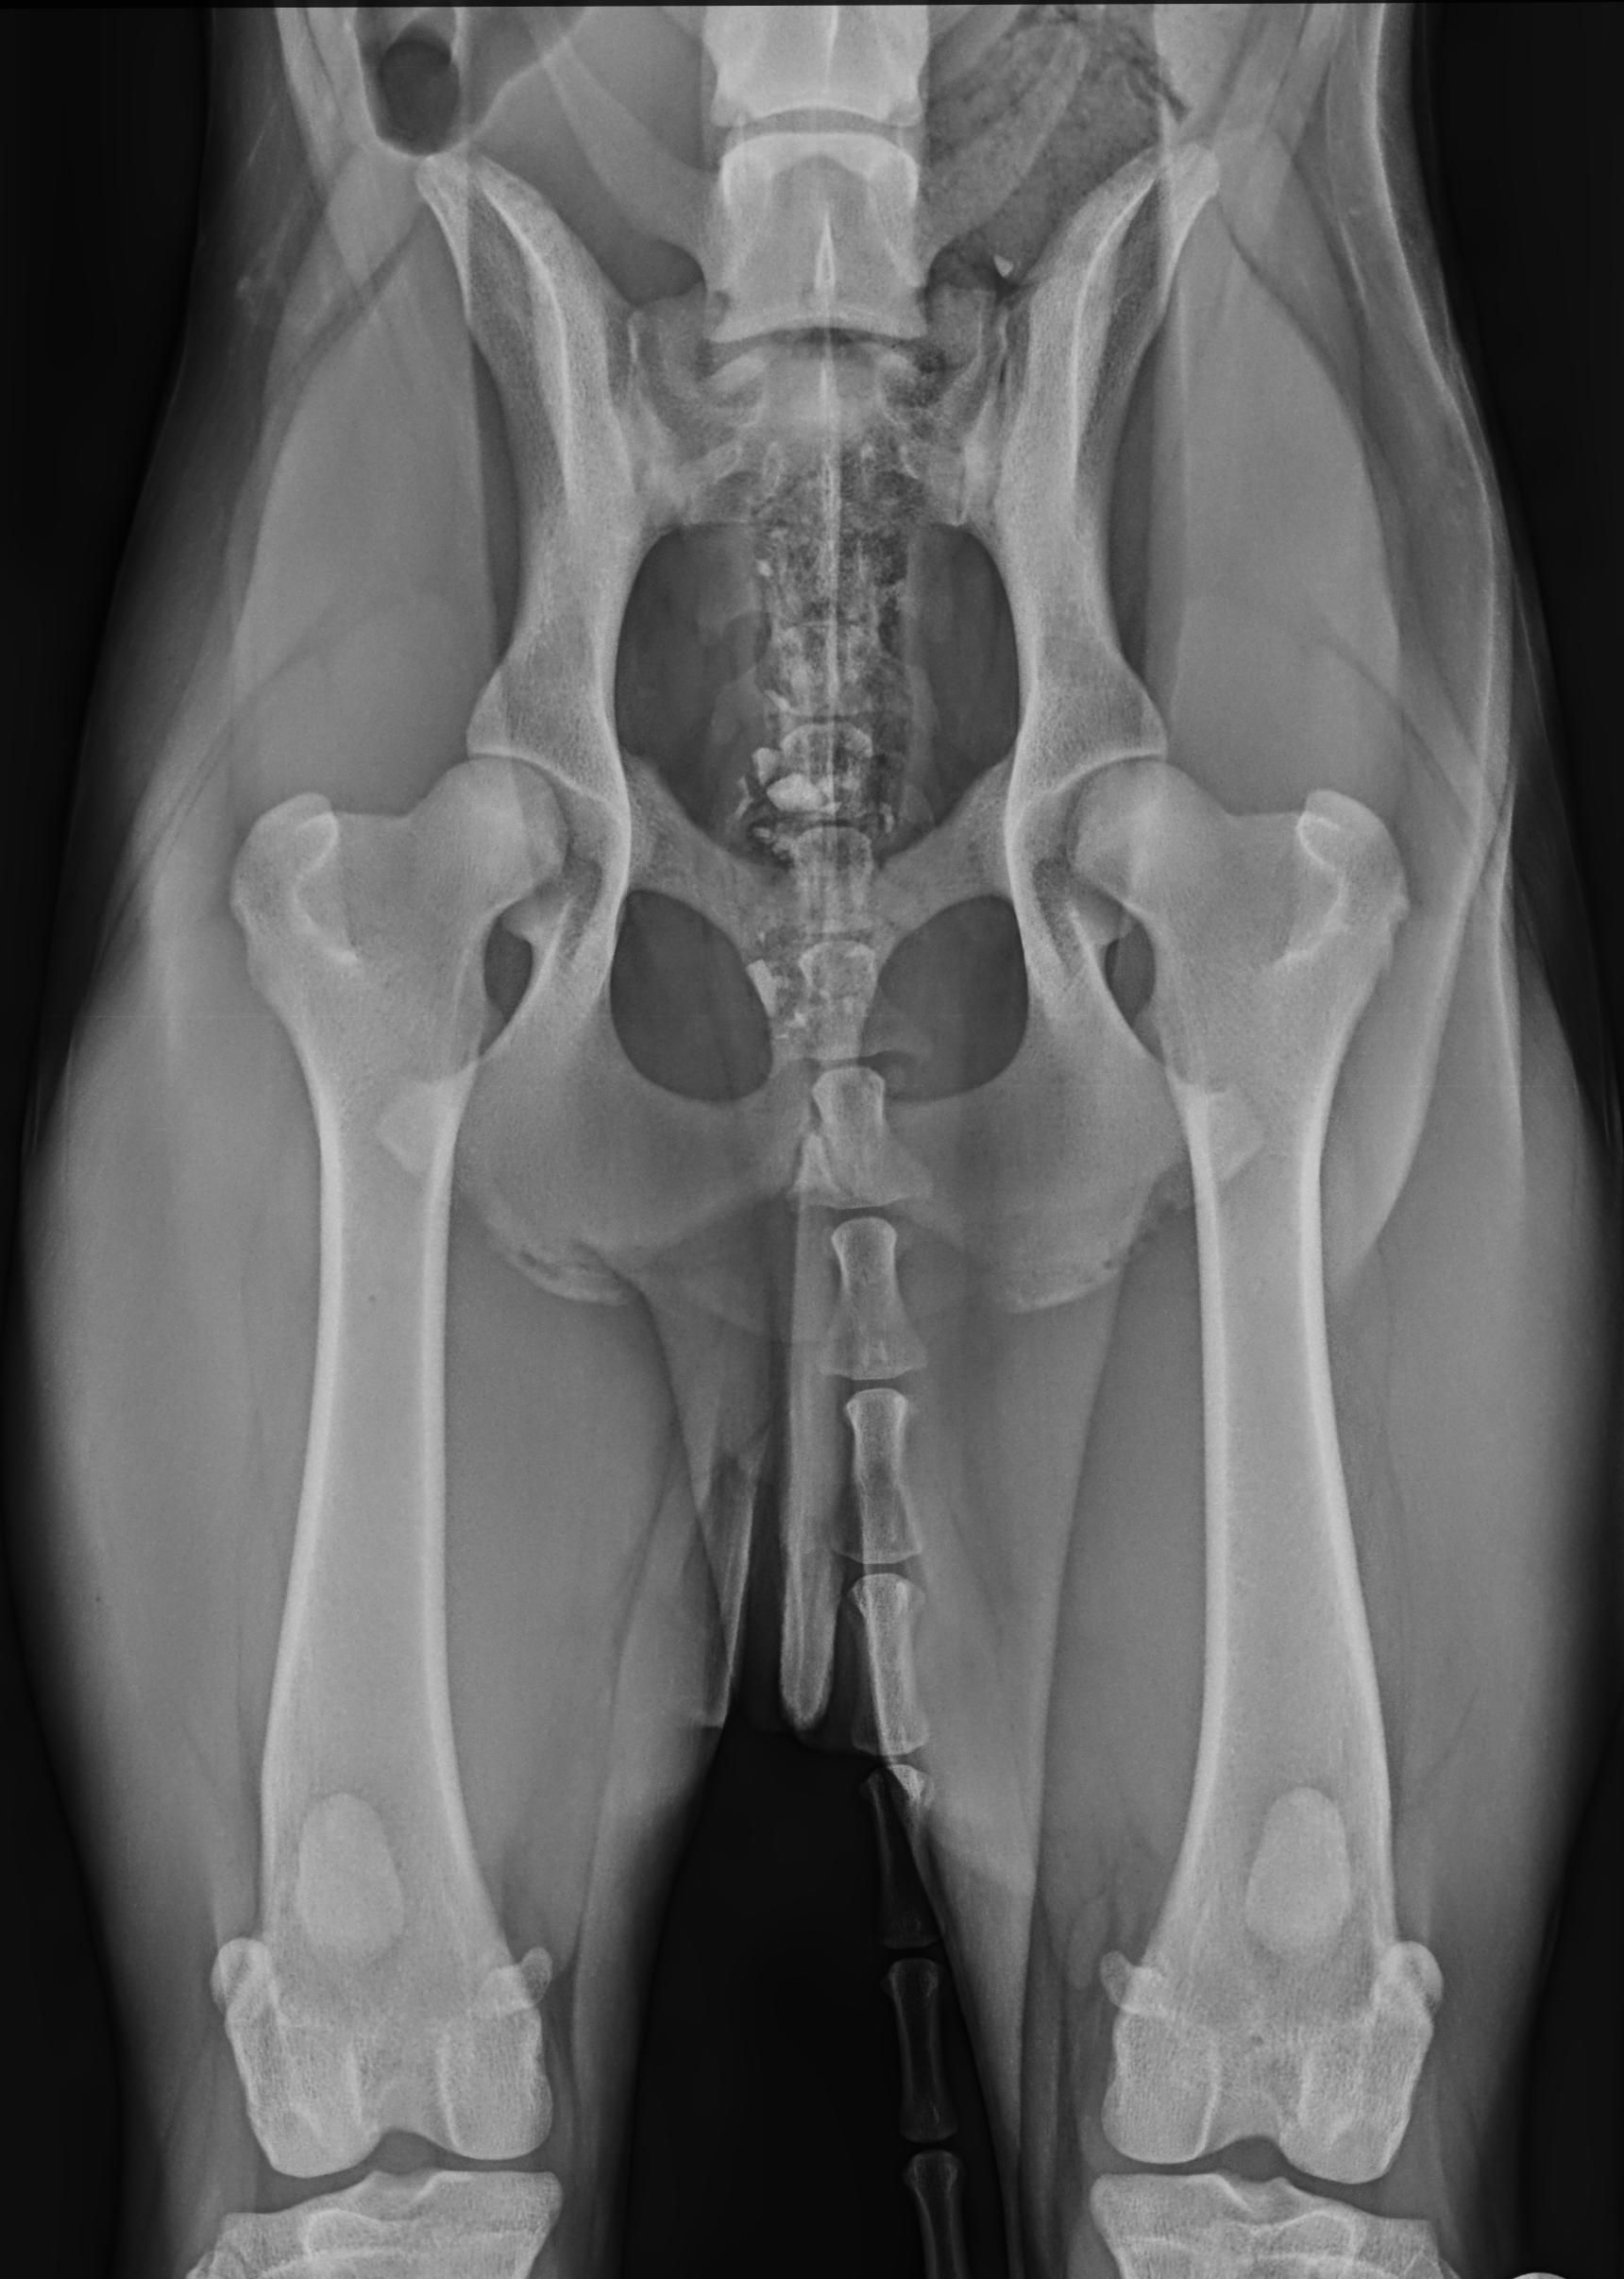

HD – Röntgenuntersuchung der Hüfte

HD steht für Hüftgelenksdysplasie und bedeutet eine Fehlentwicklung des Hüftgelenks. Betroffen sind davon vor allem Hunde großer Rassen. Die Erkrankung hat genetische (angeborene) Ursachen, aber auch Fehlfütterung oder eine Fehlbelastung können eine Rolle spielen. Eine frühzeitige Diagnose ist daher wichtig, da bis zum 10. Lebensmonat operative Korrekturen durchgeführt werden können. Werden diese bei einer HD Erkrankung nicht durchgeführt, kommt es unausweichlich zu einer Arthrose des betroffenen Gelenks. Als therapeutische Maßnahme ist dann die Implantation eines künstlichen Hüftgelenks möglich.

Daher empfehlen wir ein „Vorröntgen“ mit 6 Monaten, welches bereits sehr aussagekräftig ist. Ab dem 12. Lebensmonat kann dann ein offizielles Röntgenbild gemacht werden (zur Zuchtzulassung bzw. zur Zulassung zur Ausbildung zum Assistenzhund).

HD Grad A

HD Grad E